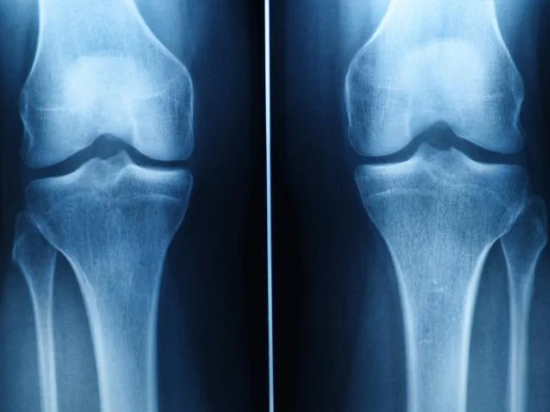

병원 진료 시 활용되는 검사

MRI 검사는 연골 손상의 위치와 범위를 파악하는 데 유용합니다. 실제로 제 지인은 무릎이 자주 붓는 증상으로 병원을 찾았다가 연골 찢어짐을 진단받았습니다.